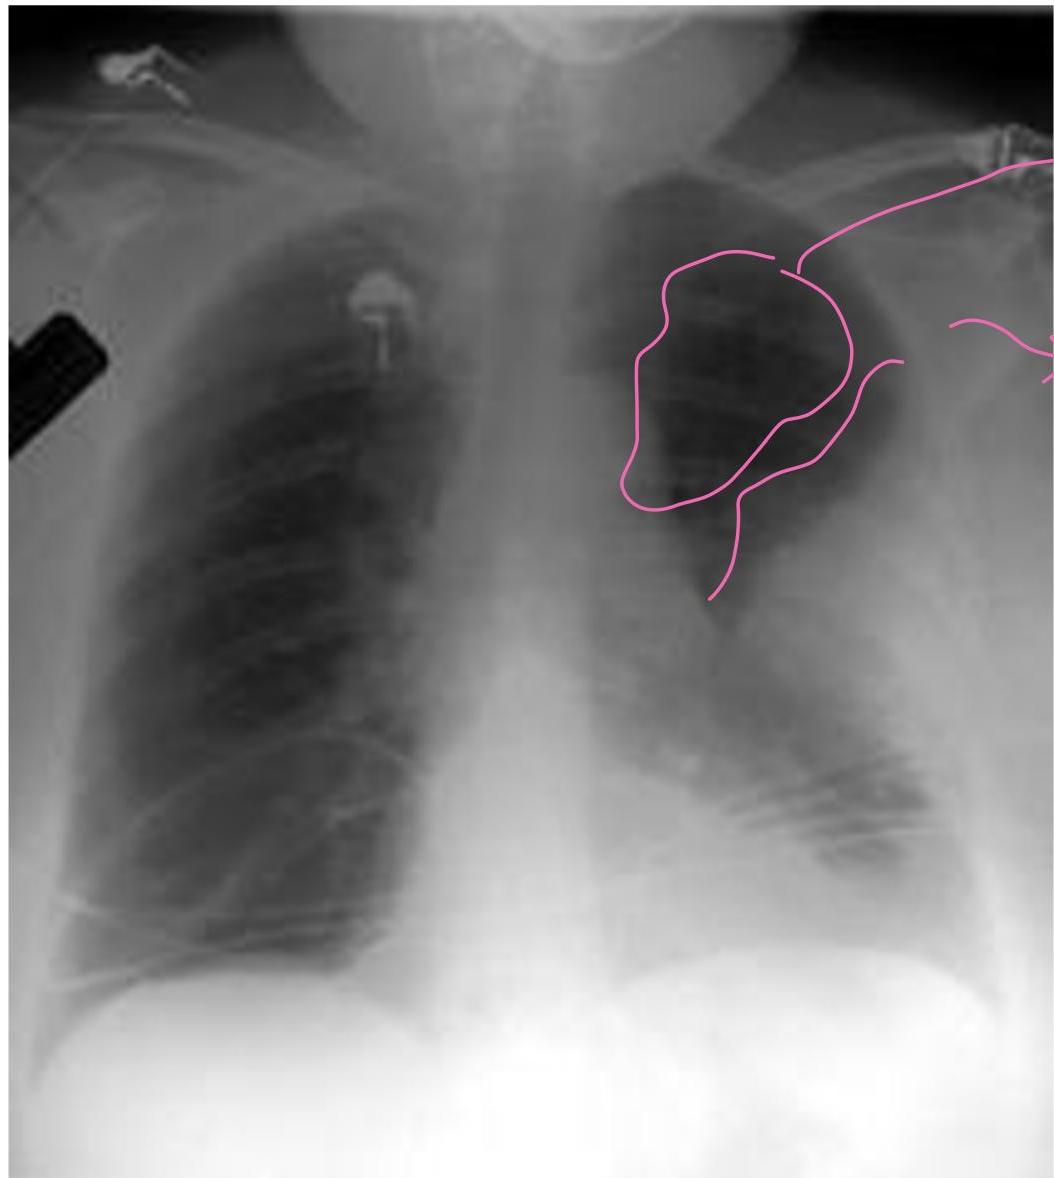

Case 1: Pulmonary Embolism (PE)

- Presentation: 62F, 3 weeks post-right THA, admitted for COPD exacerbation. Sudden onset L-sided chest pain (8/10), pleuritic, O2 sat drop (94% â 88% on 2L NC).

- Initial management: Give aspirin. Repeat ECG 4 times if no change (unstable vs non-STEMI).

- Vitals: Afebrile, HR 120, BP 110/70, RR 28.

- Exam: Accessory muscle use, EAE, loud S2.

- Labs: Positive D-dimer, Troponin 0.12 (Normal < 0.04), BNP 520.

PE

- S1Q3T3: Present in only 20% of PE.

- CXR Findings:

- Westermark sign: Clarified area (hyperlucency) secondary to oligemia.

- Hampton sign: âDome stuffedâ (hump).

- Management Plan: Give heparin (âheforinâ [sic]) and send to CT.